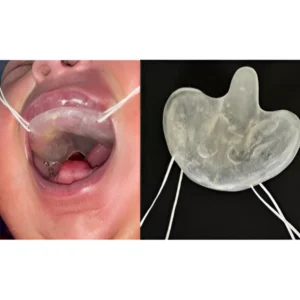

Intra-oral prosthesis is a special dental appliance designed to replace missing oral structures, support speech, help feeding, reduce dryness, and restore facial balance after surgery, injury, or birth conditions.

Obturator Prosthesis

A maxillofacial prosthesis used to close a congenital or acquired tissue opening in the hard palate.